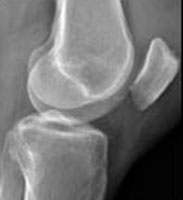

Patella Baja X-ray